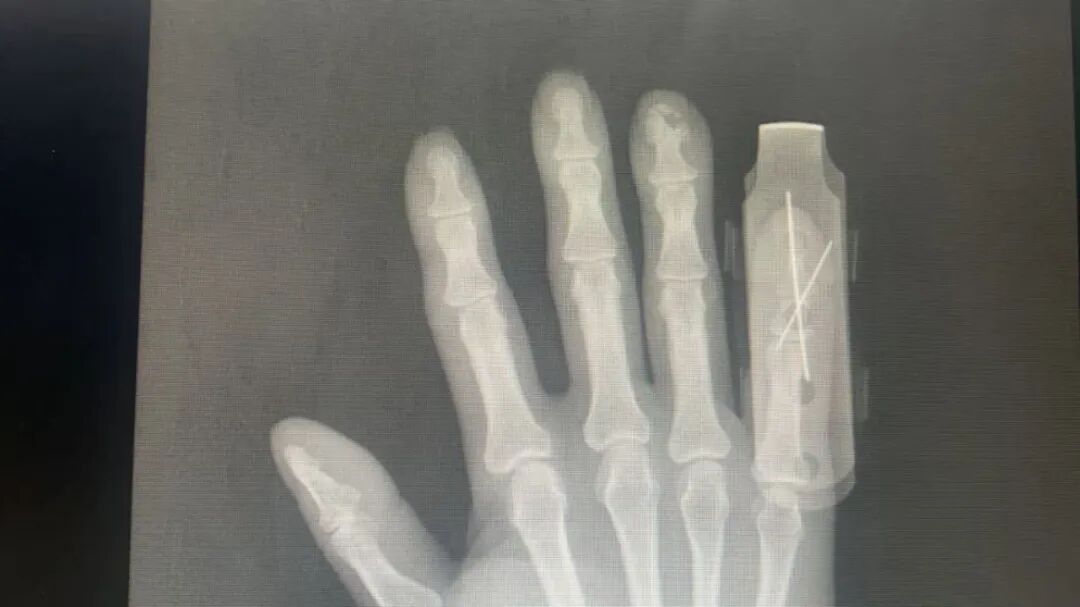

患者入院后,我院急诊绿色通道迅速开启。骨科团队第一时间接诊,经检查确诊为“右小指末节离断”,指体自远指间关节处完全分离,创面污染严重,再植条件极具挑战。影像学检查(DR)清晰显示了骨质缺损的情况。对于断指再植而言,时间就是生命力,越早手术,成活率越高。

面对焦急的患者和家属,骨科团队当机立断,在完善术前准备后,立即为患者施行了“急诊臂丛麻醉下右小指清创、断指再植及石膏固定术”。 在冰冷的手术显微镜下,一场温暖的生命接驳正在上演。我们的医生化身为“指尖上的工匠”,以比头发丝还细的缝线,在毫米级的血管与神经上“穿针引线”。清创、固定骨骼、缝合肌腱、接通动脉与静脉……每一步都要求极致精准、稳如泰山。经过数小时的紧张奋战,手术顺利完成,麻醉满意,患者安返病房。 手术成功只是第一步,术后的康复治疗同样关键。住院期间,由于患者出现血糖偏高的情况,我们立即启动多学科协作(MDT)模式,邀请内科专家会诊,制定了个性化的血糖控制方案。同时,护理团队给予了专业的镇痛、抗感染、抗凝、烤灯照射保暖及定期换药等全方位对症支持治疗,为再植指体的存活提供了最坚实的保障。 在医护人员的精心照料下,患者恢复良好。再植的右小指颜色逐渐红润,血运稳定。近日,患者顺利拆线,伤口结痂正在逐步脱落。复查X光片显示,内固定位置良好。患者对治疗效果非常满意,于2025年11月7日康复出院。 深圳永福医院骨科·手外科团队提示